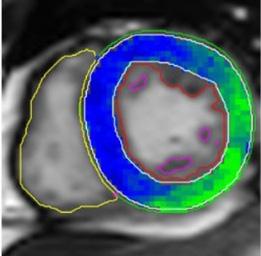

L’acquisition de cette manœuvre respiratoire et les analyses génèrent une cartographie de l’oxygénation myocardique. Rappelons que ces résultats sont dérivés d’une méthode qui n’a pris que quelques minutes à exécuter. La figure 4 présente quelques exemples des cartes obtenues.

Figure 4 : L’intensité du signal démontrant la réserve d’oxygénation du myocarde. A- Oxygénation myocardique globale chez un volontaire sain avec une augmentation globale et homogène de l’intensité du signal; B- Anomalie régionale (diminution de l’oxygénation du myocarde) chez un patient présentant une sténose coronarienne sévère; C- Réduction globale de l’oxygénation myocardique chez un patient qui souffre d’insuffisance cardiaque. La barre de couleur (à droite) fournit une légende pour les différences d’intensité du signal qui correspondent aux différences d’oxygénation myocardique. Les changements négatifs de l’intensité du signal sont mis en évidence par le bleu et le noir, ce qui représente une réponse d’oxygénation altérée, tandis que les changements positifs de l’intensité du signal sont mis en évidence par le vert, ce qui représente une réponse d’oxygénation saine.